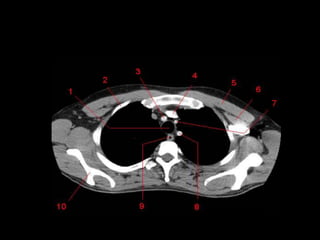

TC mediastino superior